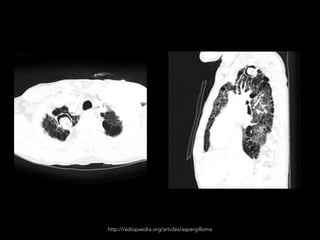

ASPERGILOMA

• No hay invasión tisular.

• Conglomerado de hifas con moco y detritus celulares.

• Se aloja en una caverna existente o bronquio ectásico.

• Tuberculosis y sarcoidosis.

• Generalmente son únicos.

• Hemoptisis.

Yale Rosen,

M.D.http://radiopaedia.org/articles/aspergilloma

http://radiopaedia.org/articles/aspergilloma

ASPERGILOMA • No hayinvasión tisular. • Conglomerado de hifas con moco y detritus celulares. • Se aloja en una caverna existente o bronquio ectásico. • Tuberculosis y sarcoidosis. • Generalmente son únicos. • Hemoptisis. Spectrum of Pulmonary Aspergillosis: Histologic, Clinical, and Radiologic Findings Tomás Franquet, Nestor L. Müller, Ana Giménez, Pedro Guembe, Jesus de la Torre, and S. Bagué RadioGraphics 2001 21:4, 825-837

• #8 Otras condiciones preexistentes: quiste broncogénico, secuestro pulmonar, pneumatoceles sec a pneumocystis girovechy